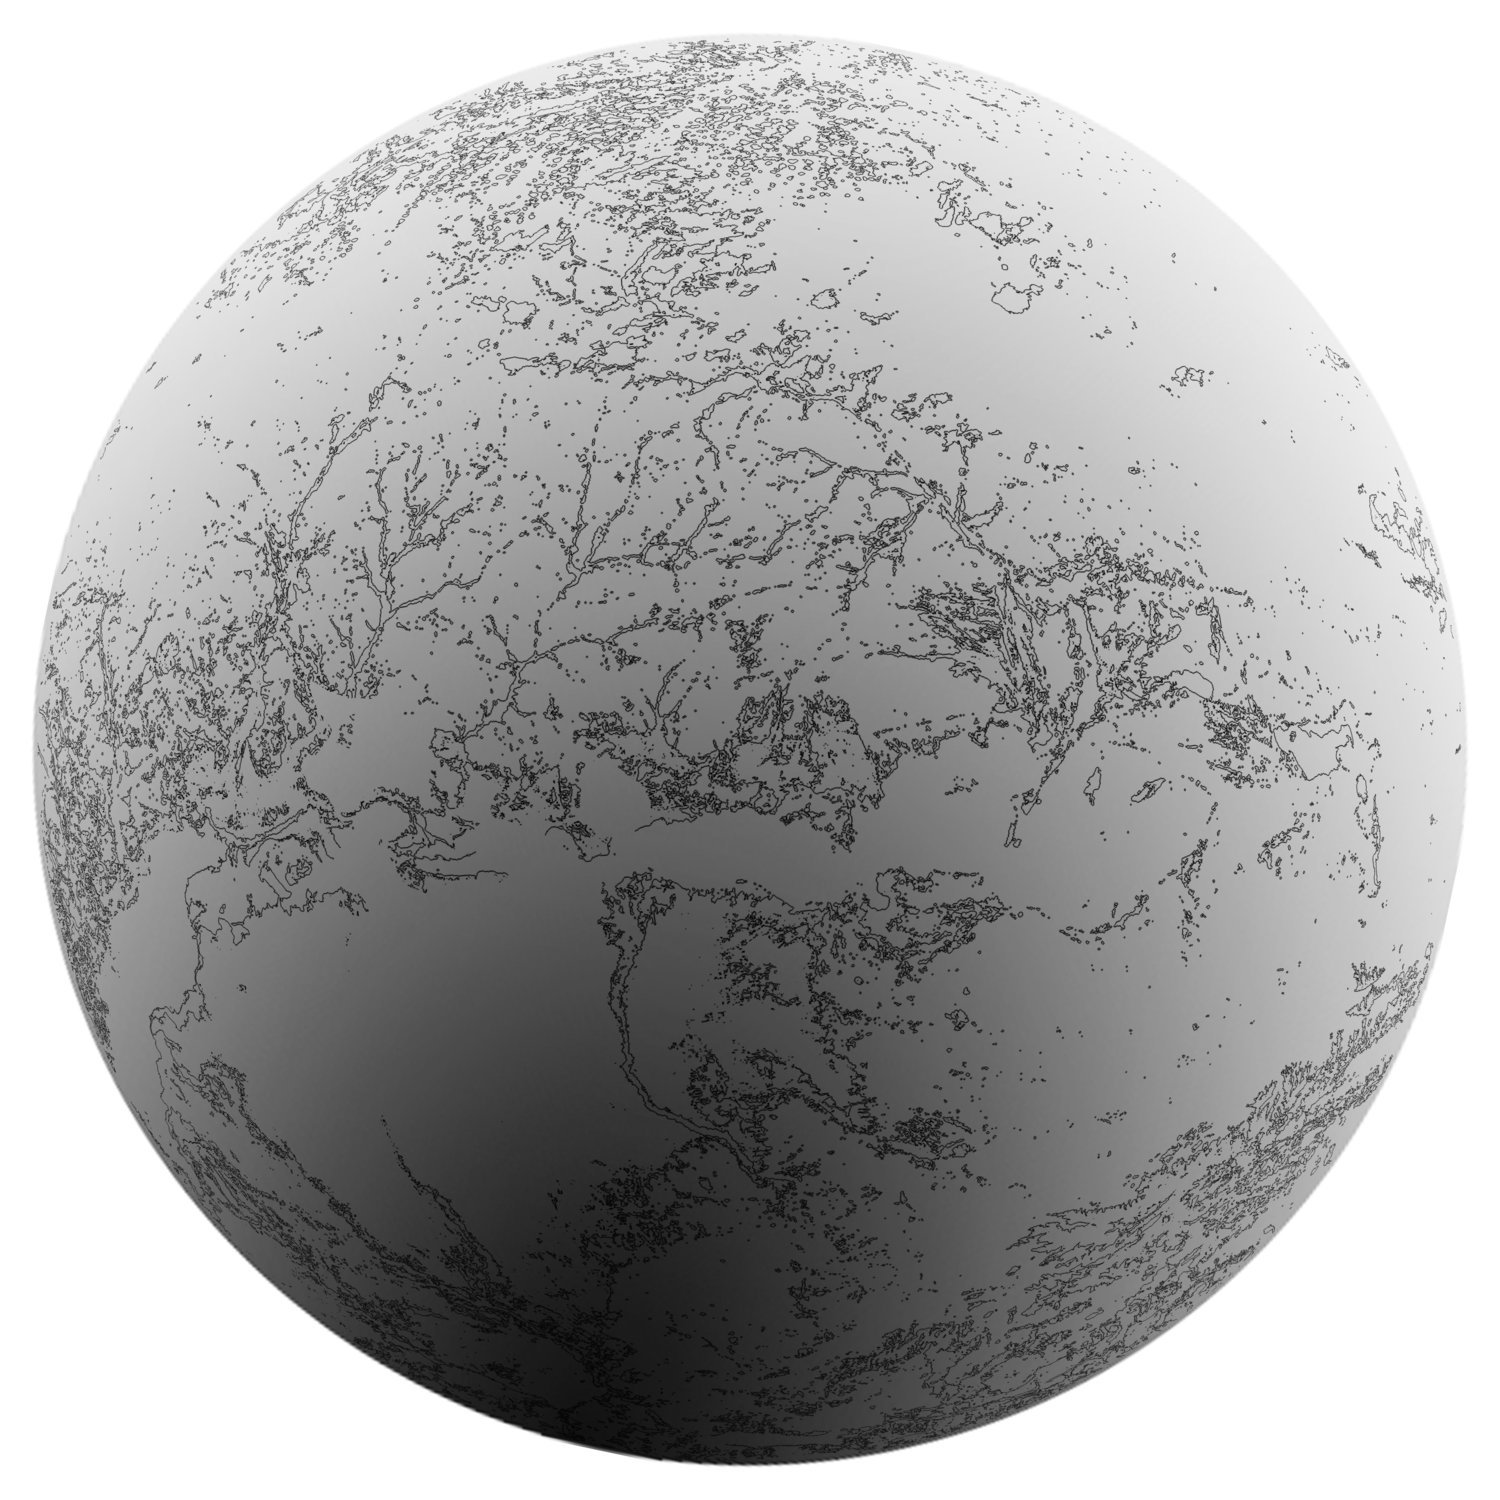

MRI 17910, Jakob Dwight, 2013, Digital print /Duratrans backlit film for lightbox

MRI, Jakob Dwight, 2013, digital print